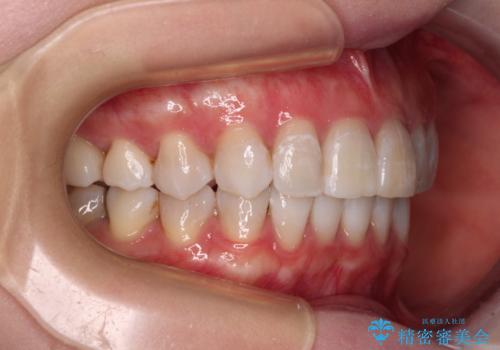

前歯の突出感とデコボコをインビザライン矯正で改善

- 上下前歯の突出感とデコボコを気にして来院された患者様です。

インビザラインによる上下歯列の側方拡大と後方移動、IPR(歯と歯の間を削る)にるスペースの獲得により歯列を整えることとしました。

骨格的な左右差があったため、上下の正中を合わせることができませんでした。

骨格の差は改善できないため、奥歯の咬み合わせに物足りなさを感じましたが、奥歯の咬み合わせによる不自由はなく、口元の突出感も改善することができました。